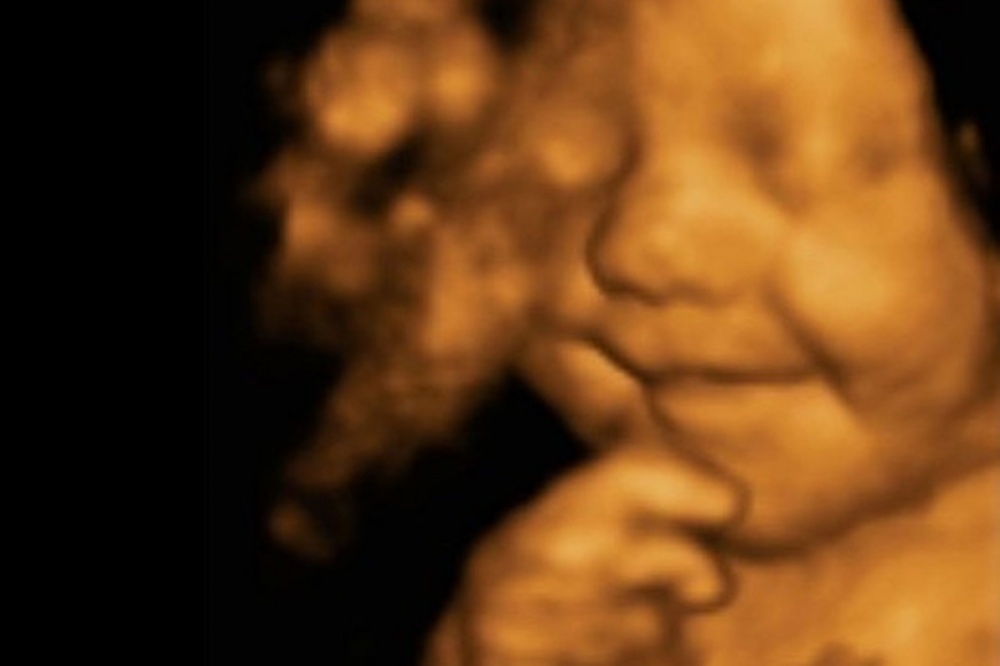

نشرت صحيفة التليغراف البريطانية صورا قالت إنها لطفل لم يتوقف عن الابتسام، منذ أن كان جنينا في شهره الخامس وحتى الآن، مشيرة إلى أن صورة أخذت للطفل "ليو ديفيد هارغريفز كانت وهو جنين بنظام الـ 4D.

الاشعة فوق الصوتية 4D، أخذت عندما كانت الأم ايمي حاملا في الأسبوع الـ31، وظهر جليا وبشكل واضح الجنين ليو وهو مبتسم، فيما قال والد الطفل ليتون هارغريفز، إن الطفل استمر في الابتسام منذ أن ولد في 30 يونيو وحتى الآن.